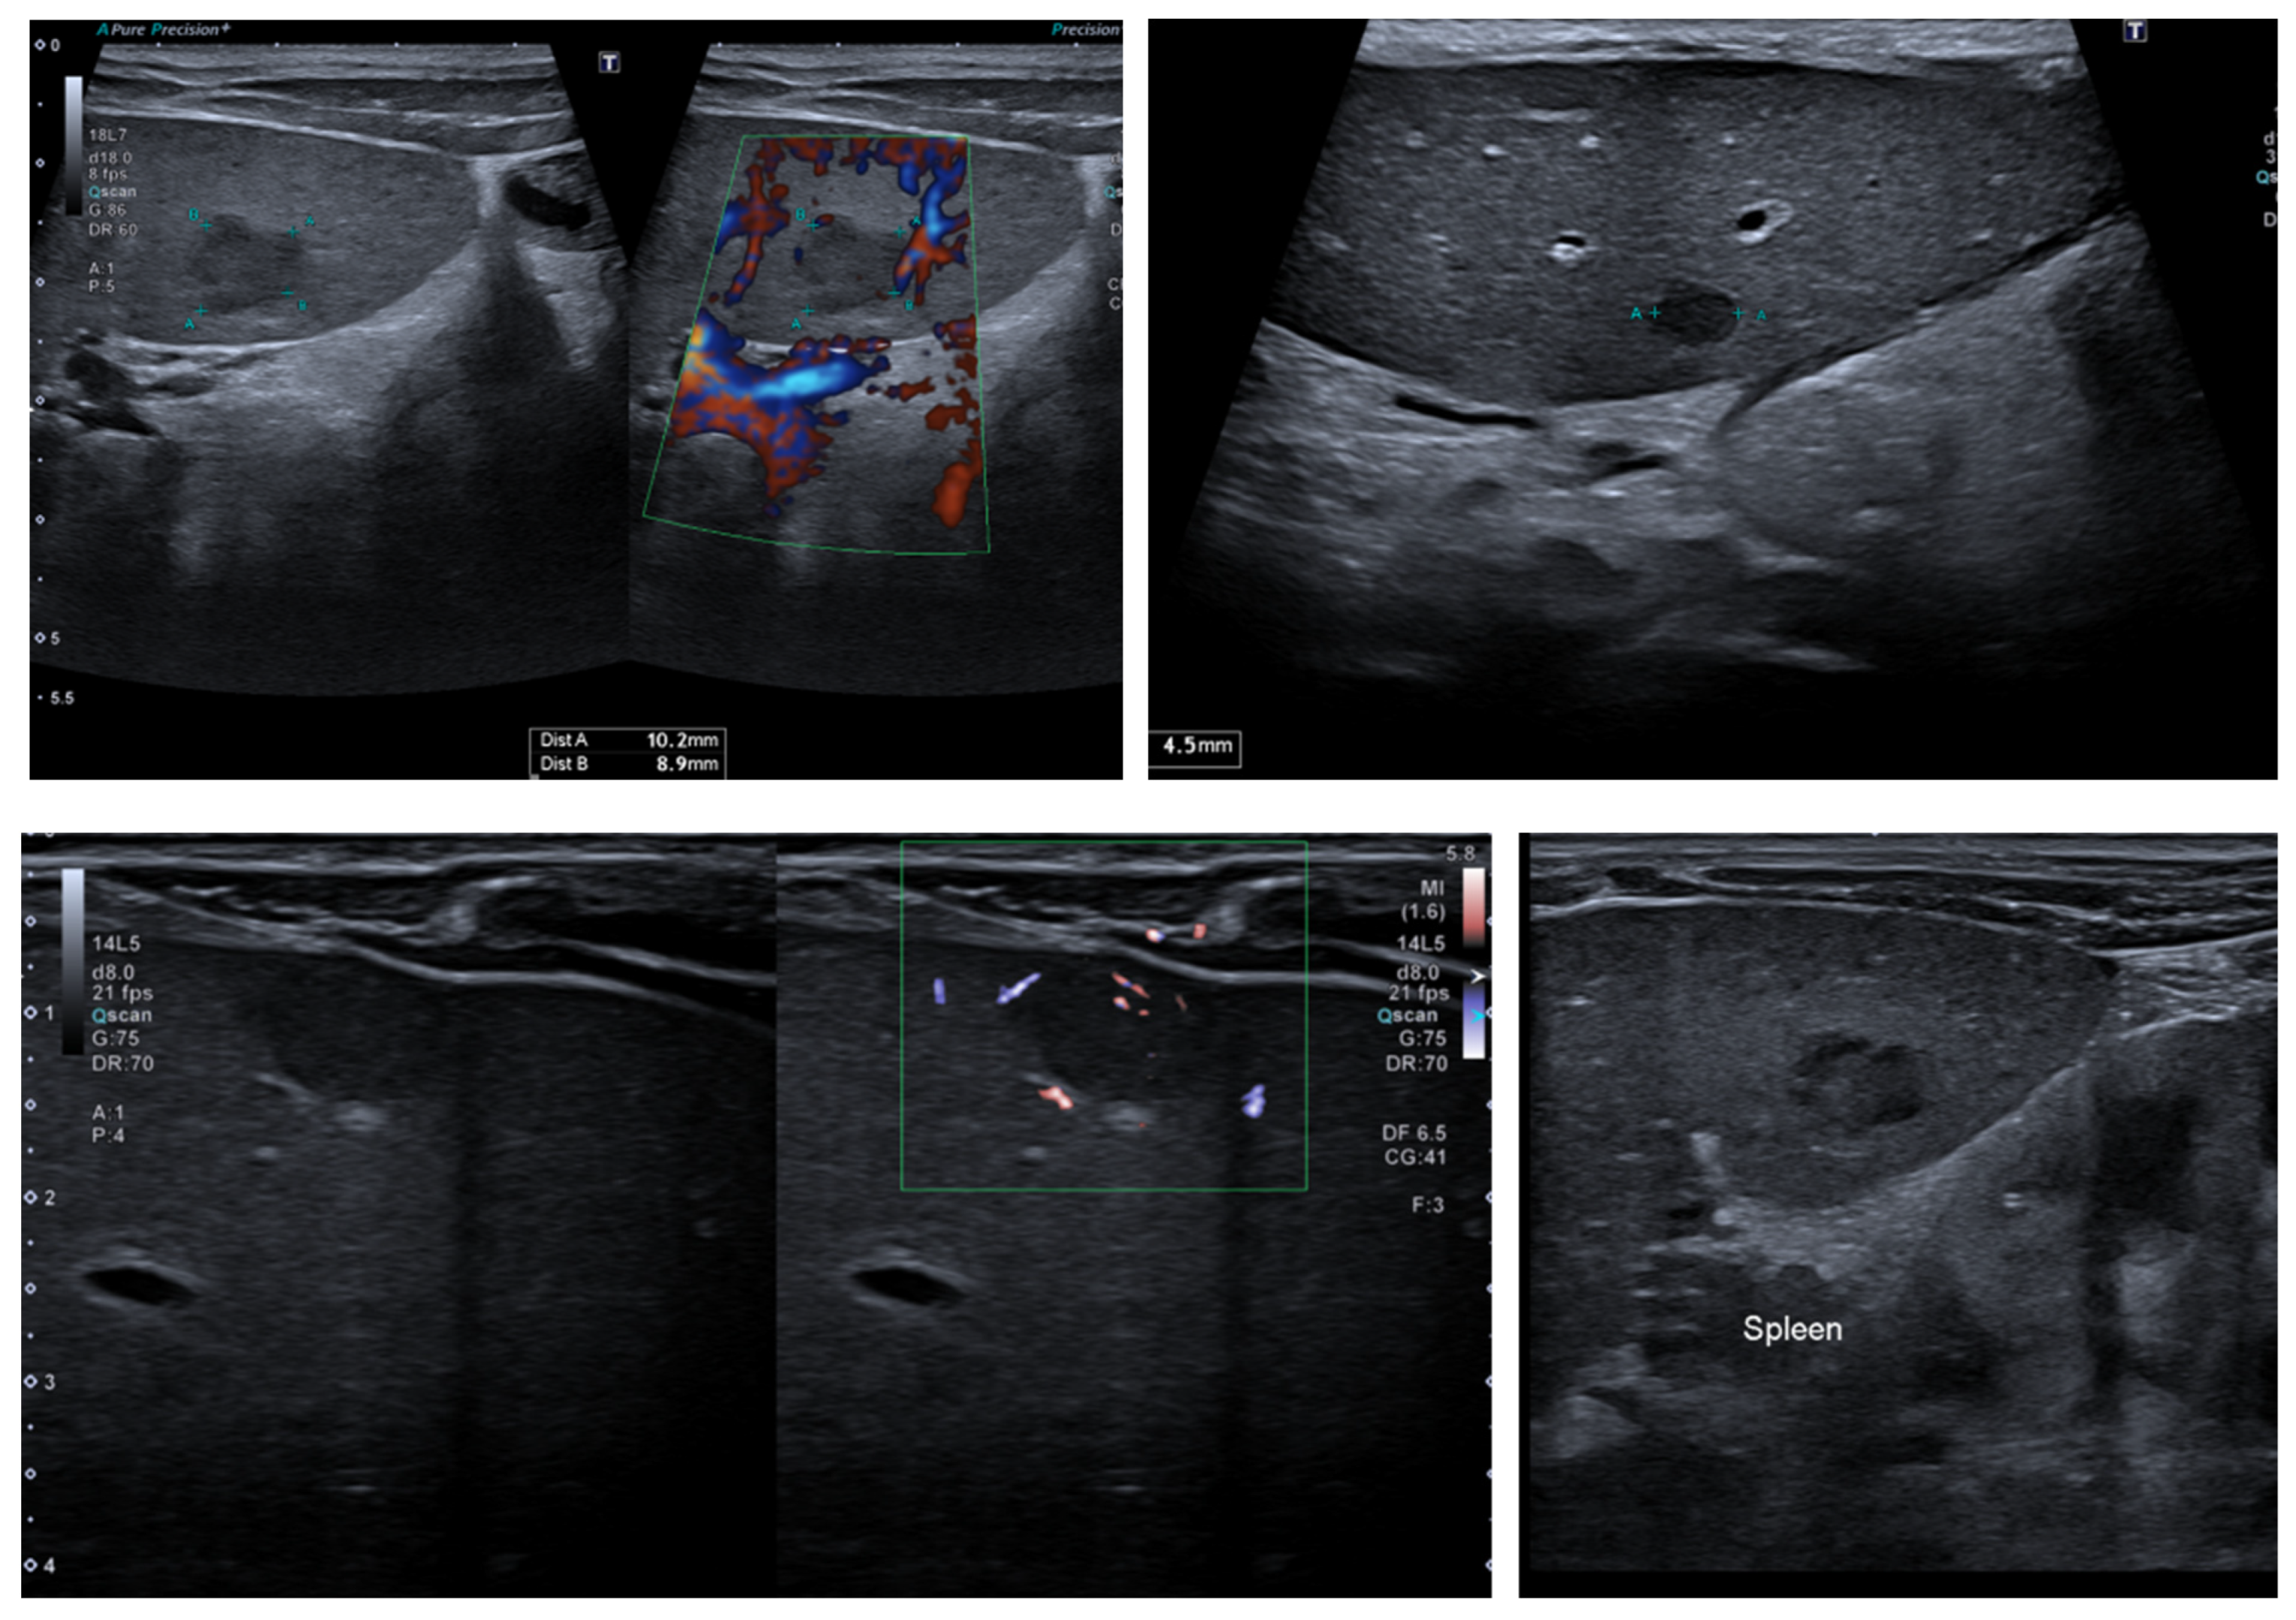

After one week at home, the patient’s clinical condition worsened, with significant weight loss (800 g) down to 7.900 g (z-score −1.93 DS), a height of 74 cm (z-score −0.77 DS), a weight for age z-score of −2.2 DS, a ponderal index (PI) of 0.79, and a total refusal of food. Thus, we started feeding her with a nasogastric tube. The neurological evaluation did not reveal any signs suggestive of the progression of the underlying disease. Also, we periodically evaluated the liver function, detecting a slight increase in transaminases and cholestasis enzymes. The abdominal ultrasound revealed four hypoechoic lesions, similar to granulomas (three on the liver and one on the spleen) (Figure 1). As tests for the Epstein-Barr virus and Cytomegalovirus’s viral load were positive, the most likely explanation was the onset of post-transplant lymphoproliferative disease (PTLD).

Figure 1. The ultrasound exam revealed three lesions on the liver and one on the spleen.